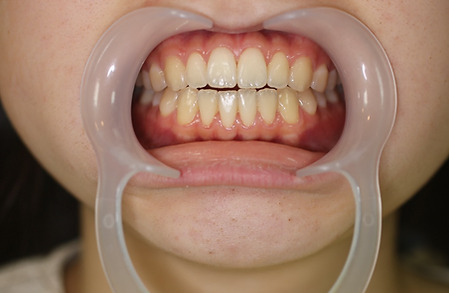

2ホワイトニング【治療例1】

治療前

治療後